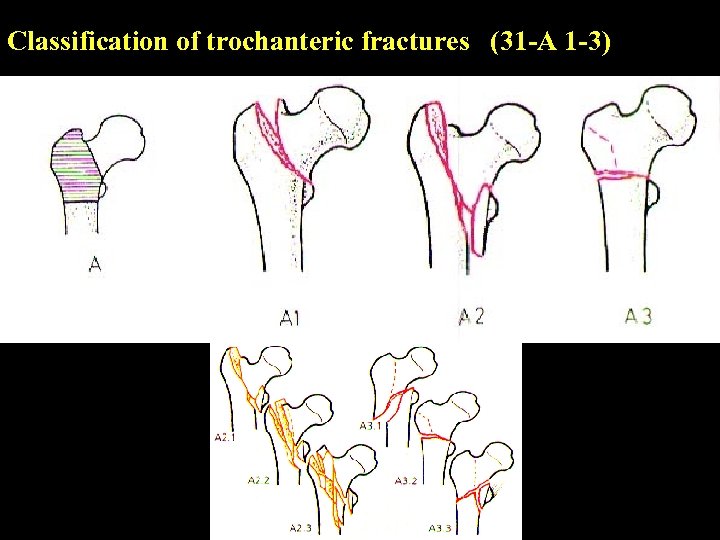

Classification of trochanteric fractures (31 -A 1 -3)

Classification of trochanteric fractures (31 -A 1 -3)